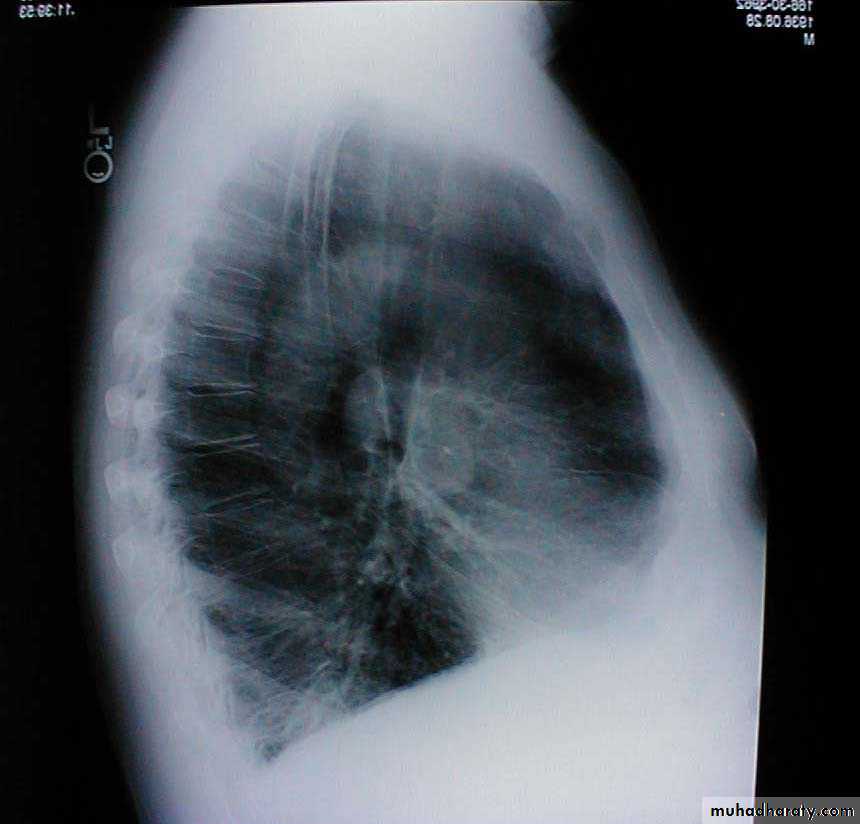

Barrel chest: Associated with emphysema and lung hyperinflation. Accompanying xray also demonstrates increased anterior-posterior diameter as well as diaphragmatic flattening.

ظاهر